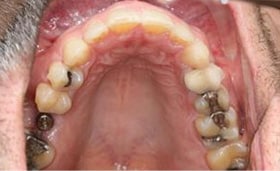

Using Clarity™ Aligners in Interdisciplinary Treatment to deliver esthetic solutions in collaboration with restorative specialists.